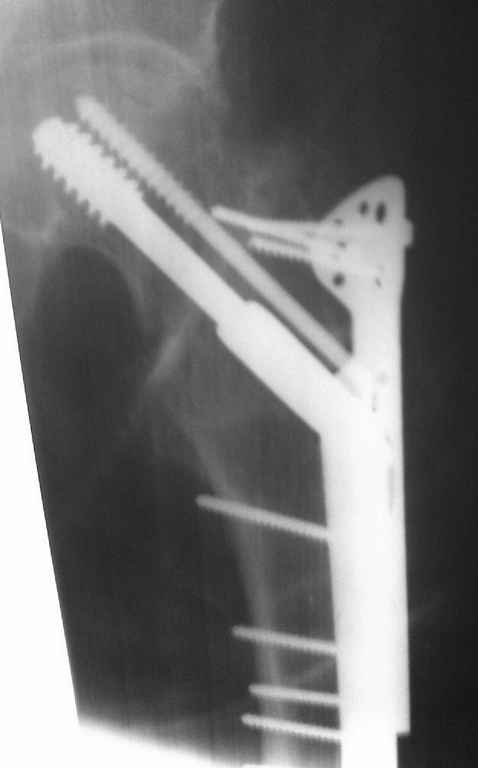

На снимках ложный сустав шейки бедра, несостоятельность фиксации. По положению шурупа можно предсказать ложный сустав, например, если screw backup за кортикальный слой около 15-20 мм, и также изменение угла от первоначального.

№2-3 типичная ошибка несоблюдения концепции параллельности шурупов, нарушение-фиксация поперечным допольнительным шурупом для приближения отломка в результате не сработало метод параллельных шурупов